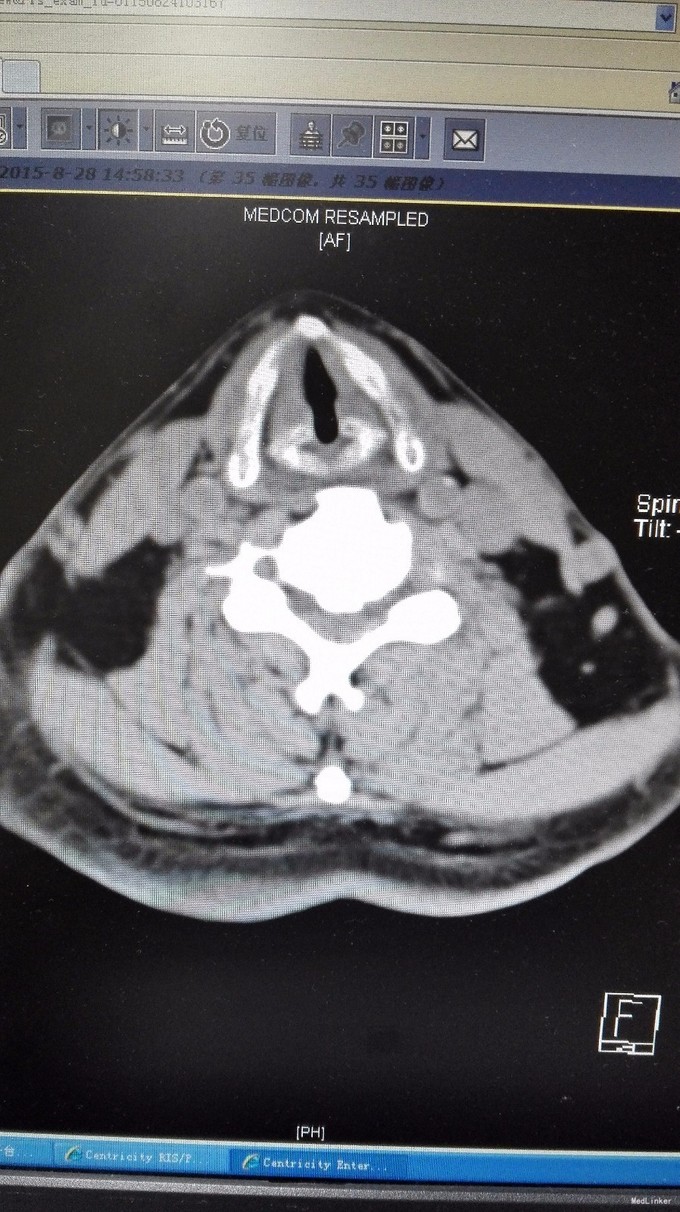

查体:双手麻木感,肱三头肌肌腱反射活跃,左侧髂腰肌4级,臂丛牵拉实验阴性,椎间孔挤压实验阴性。 辅查:CT:C2-7椎间盘突出,继发性椎管狭窄,OPLL,OFL。

诊断:混合型颈椎病(脊髓型+神经根型) 治疗:颈后路3-7单开门椎管扩大成型术(锚定法)